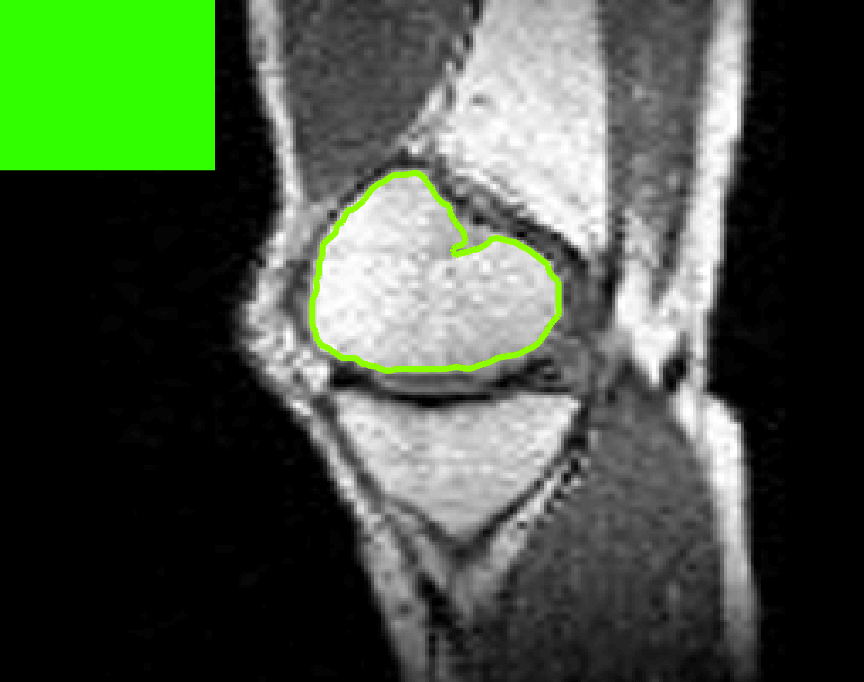

Test Images. We will perform initial tests on the images shown in Figs. 5–7. We have provided the ground truth and initialisation used for each image. Test Images 1–3 are synthetic, Test Image 4 is an MRI scan of a knee, Test Images 5–6 are abdominal CT scans, and Test Images 7–9 are lung CT scans. They have been selected to present challenges relevant to the discussion in §2. We focus on medical images as this is the application of most interest to our work. In the following we will discuss the results in terms of synthetic images (1–3) and real images (4–9). We also test the proposed approach on a larger data set of 30 CT images (a sample of which is presented in Fig. 18), comparing against existing selective methods detailed in §3.

Real Images. In Fig 12 we present results for Test Images 4–6. Here, the proposed model performs in a similar way to its competitors because these images are more typical selective segmentation problems in the sense that there is a clear distinction between the foreground and background intensities. In particular, the values in each case are: Test Image 4 , Test Image 5 , and Test Image 6 . It can be seen that the proposed model is competitive compared to previous approaches. The performance is quite poor for Test Image 5, but is arguably still the best for this challenging case. In Fig. 13 we present results for Test Images 7–9. Here the proposed model outperforms previous approaches significantly for each image. This is mainly due to the type of image considered. Specifically, the true intensities are: Test Image 7 , Test Image 8 , and Test Image 9 . The proposed model is capable of achieving results where , with other models failing completely in these cases.

Here we aim to address the question of whether each model is capable of achieving an accurate result. In other words, assuming that factors such as parameter and user input sensitivity are ignored, how successful is each approach. In Table 1 we present the optimal TC values for each model found from the tests described in the previous section, with the highest value in bold. We include values for CAC Nguyen:12 and SRW SRW , which we have obtained by iteratively refining the user input and running the algorithm. It is worth mentioning that we are using the authors’ implementation of each method. For each image, the results presented in Table 1 are the most accurate we could obtain given a reasonable level of input (comparisons with identical input are discussed in §7.4). Immediately we can see that the proposed model consistently outperforms the other models in terms of accuracy for the test images (RSF equals it for Test Image 1, SRW equals it for Test Images 1-3, and beats it for Test Image 8). Below we will discuss some relevant details of the results, again by splitting the test images into synthetic and real.

Real Images. In Table 1 we can see that the proposed model is the most successful in terms of optimal accuracy. It is worth noting some inconsistency in the other models, with all but GAV having results that fall below TC for at least one image. GAV performs well for Test Images 4–9, with the proposed model slightly outperforming it in each case. It is worth reminding the reader that for GAV the parameters have been refined for each example. Fixing this results in more variability in the quality of results. The proposed model has no such parameter optimisation between examples. CAC and SRW perform reasonably well for these images, although are sometimes substandard for Test Images 4-7. This is despite extensive refinement of the user input to achieve an acceptable result. We present the optimal results for Test Image 9 in Fig. 14. Here we can see how much variation there is in the quality of results for this lung CT image. CAC and SRW are competitive in this instance. Of the remaining approaches GAV is the most competitive (TC ), but is visually inadequate. Two other models (CV, HYB) fail completely. In this case, the problem looks quite straightforward and yet other fitting terms are insufficient to produce a good result. Again, the proposed model tends to be superior in cases where and is capable of achieving very good results for all the images considered. This highlight the advantages of the proposed fitting term.